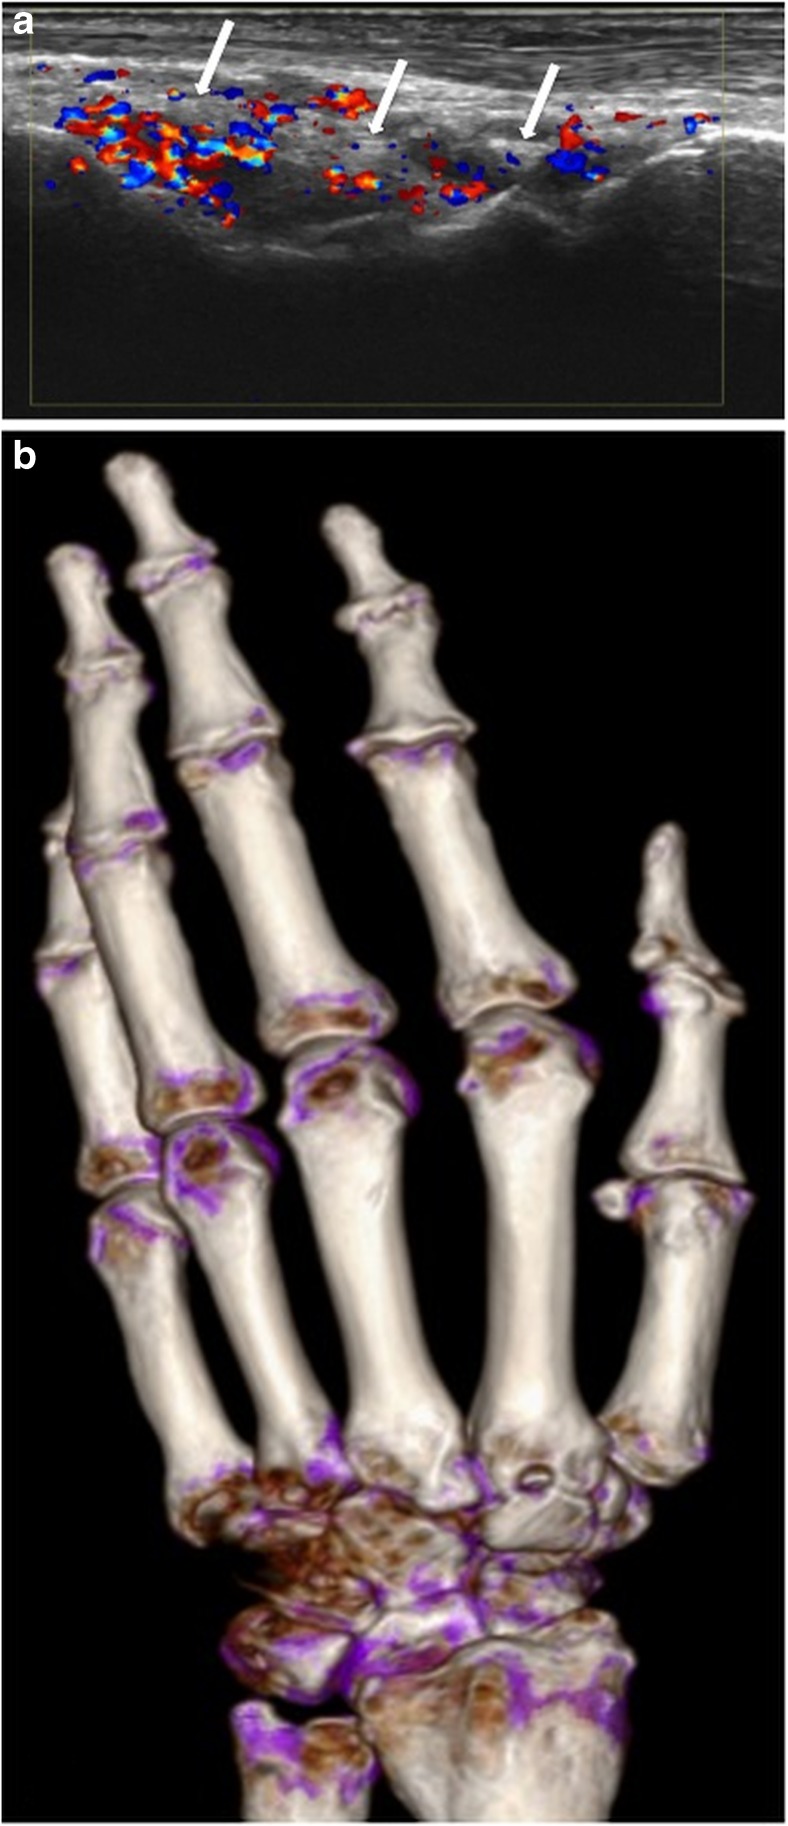

Fig. 3.

Left hand of a 63-year-old male patient. a Longitudinal US scan of the dorsal wrist showing hypoechoic thickening, extensive hyperemia and echogenic deposits (white arrows) in RC and IC joints, rated as indeterminate. b DECT 3D volume rendered image of the same hand showing no MSU deposits, but severe osteoarthritis at RC, IC and carpometacarpal joints in terms of osteoarthritis

Discussion

The DCS was the most frequently detected US sign for the diagnosis of gouty hand and wrist arthritis with a sensitivity of 76% for intra-articular gout, with an overall sensitivity of 65% (Fig. 4). For the extra-articular compartment in terms of gouty deposits in tendons DECT was superior for delineation and characterization [22]. Our study is the first to give a detailed description of MSU depositions in both the intra- and extra-articular compartments of the hands and wrists with comparison of US to DECT.